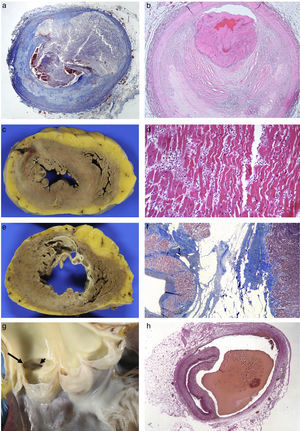

Coronary artery diseaseThis is the most common heart disease in forensic practice given that 60–90% of SDs are attributed to this disease. We found ischaemic heart disease, predominantly chronic, both of the coronary arteries (with stenosis >75% of the lumen) (92%), and of the myocardium (scars) (39%) in 65% of the SDs studied in our department.6 The chronic stenotic lesions of the coronary arteries are divided into two large groups: stable plaques with thick fibrous capsules on a lipid or fibrous necrotic centre (atheromatous plaques themselves) or pathological intimal hyperplasia (juvenile atherosclerosis).7 The incidence of acute coronary thrombosis is variable (we found it in 27% of cases),6 and it can be caused by the rupture of atheromatous plaques with thin fibrous capsules (vulnerable plaques) which result in the content of the plaque being excreted and intraluminal fibrin-platelet thrombosis (Fig. 1A); or to endothelial denudation of the plaque (erosion) with occlusive or mural platelet thrombosis (Fig. 1B); this type occurs in stable atheromatous plaques or in pathological intimal hyperplasia. Plaque rupture occurs more frequently in males aged 35–80 with classic risk factors (hyperlipidaemia, smoking, diabetes) and erosion occurs more frequently in younger people associated with smoking and genetic factors.7 The link between cocaine use and early atheromatosis with coronary thrombosis is important in young people.8,9

(A) Rupture of vulnerable plaque with secretion of content (Masson's trichrome 2×). (B) Plaque erosion and occlusive platelet thrombosis (HE, 4×). (C) Anterior transmural AMI with wall rupture. (D) AMI >24h: necrosis due to coagulation of the myocytes and intense neutrophilic inflammatory infiltrate (HE, 20×). (E) Previous transmural anteroseptal infarction with marked wall thinning and endocardial fibrosis. (F) Dense collagen scar with extensive adipose metaplasia (Masson's trichrome 4×). (G) Origin of the two coronary arteries in the right sinus (long arrow in left ostium; short arrow in right ostium). (H) Coronary artery dissection with haematoma between the middle layer and the external elastic lamina (Weigert, 2×).

Coronary thrombosis causes AMI but, when death occurs at an early stage (in less than 12h) from the coronary occlusion, there is no time for the ischaemic necrosis in the myocardium to be visible. The dating of the AMI is a very important issue in forensic pathology, because the deceased frequently present with symptoms hours before death for which medical attention is requested. Table 1 summarises the chronology of an infarction adapted from Schoen10 (Fig. 1C–F).

Congenital abnormalities originating in the coronary arteries account for the second biggest cause of SD in competitive American athletes,11 and for 2–4% of SDs in recreational athletes in our setting.12 Several types can be found: origin of the left coronary artery in the pulmonary trunk or in the right coronary sinus (Fig. 1G); origin of the right coronary artery in the left sinus; or origin of either of the two several mm above the sinotubular junction.13 The origin of the left coronary artery in the pulmonary artery trunk results in the left ventricle (LV) receiving poorly-oxygenated blood, which induces the development of collateral branches from the right coronary artery to compensate for hypoxia but, in situations of greater oxygen demand, such as sporting activity, it can cause SD.6,12 The consequences of the coronary artery originating from the opposite sinus depend on the acute angle of the ostium and its path from its origin to being located in its normal position. The acute angle and the course of the anomalous coronary artery between the aorta and the pulmonary artery, or embedded in the aortic wall, makes them susceptible to collapsing during physical exercise.

Spontaneous coronary artery dissection consists of the formation of a haematoma between the middle layer and the external elastic which causes its lumen to collapse (Fig. 1H). It tends to affect the left coronary artery and its branches and its origin may be spontaneous or iatrogenic due to intimal rupture in coronary intervention techniques. Its spontaneous form occurs more frequently in women, related to pregnancy, the postpartum period, fertility treatment and the use of contraceptives. It is also associated with collagenopathies, use of cocaine, smoking, HTN, intense physical exercise, weight lifters or even prolonged spells of sneezing. Eosinophils are often microscopically identified in the adventitia.13